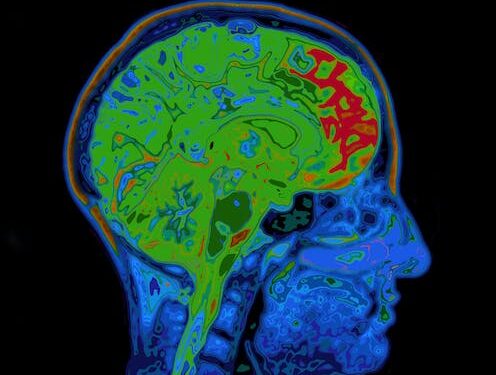

To study glutamate and Gaba, we used a high-strength magnet (called 7-Tesla) to perform magnetic resonance spectroscopy. This technique detects radio frequency electromagnetic signals produced by the atomic nuclei in molecules. This helps scientists to measure what kind of chemicals exist there – and their concentration.

This allowed us to detect and measure glutamate and Gaba levels separately in different brain regions. We specifically looked at two brain regions toward the front of the brain called the anterior cingulate cortex (ACC) and the supplementary motor area (SMA).